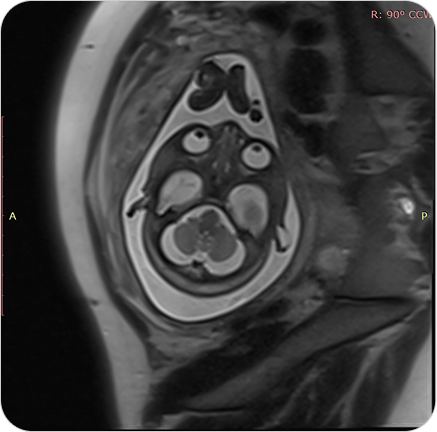

Resonancia Magnética Fetal

La resonancia fetal es un estudio no invasivo que permite observar con gran detalle el desarrollo del bebé en el útero. Es un complemento ideal de la ecografía cuando se necesita información más precisa.

La resonancia magnética fetal permite obtener imágenes detalladas del bebé durante el embarazo, sin utilizar radiación. Se utiliza como complemento del ultrasonido cuando se detectan hallazgos que requieren evaluación más precisa.

¿PARA QUE SE UTILIZA?

- Evaluar el desarrollo del sistema nervioso central fetal (cerebro y médula espinal).

- Detectar malformaciones cerebrales o anomalías estructurales.

- Valorar la anatomía de órganos internos en casos complejos.

- Confirmar o descartar hallazgos dudosos en ecografías.

- Planificar tratamientos o decisiones perinatales junto con el equipo obstétrico.

¿POR QUÉ ES UN ESTUDIO DESTACADO?

- No invasivo y seguro para la madre y el bebé.

- Alta definición de imágenes incluso en embarazos avanzados.

- Permite tomar decisiones médicas informadas y personalizadas.

- Evita resonancias post-natales.

Resonancia Magnética Fetal

La resonancia fetal es un estudio no invasivo que permite observar con gran detalle el desarrollo del bebé en el útero. Es un complemento ideal de la ecografía cuando se necesita información más precisa.

La resonancia magnética fetal permite obtener imágenes detalladas del bebé durante el embarazo, sin utilizar radiación. Se utiliza como complemento del ultrasonido cuando se detectan hallazgos que requieren evaluación más precisa.

¿PARA QUE SE UTILIZA?

- Evaluar el desarrollo del sistema nervioso central fetal (cerebro y médula espinal).

- Detectar malformaciones cerebrales o anomalías estructurales.

- Valorar la anatomía de órganos internos en casos complejos.

- Confirmar o descartar hallazgos dudosos en ecografías.

- Planificar tratamientos o decisiones perinatales junto con el equipo obstétrico.

¿POR QUÉ ES UN ESTUDIO DESTACADO?

- No invasivo y seguro para la madre y el bebé.

- Alta definición de imágenes incluso en embarazos avanzados.

- Permite tomar decisiones médicas informadas y personalizadas.

- Evita resonancias post-natales.